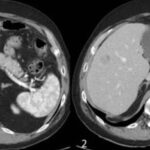

En las lesiones hipervasculares que reportamos se incluye al CHC, al hemangioma y a la HNF que fueron mejor caracterizadas en la fase arterial del estudio dinámico por TCMD. se analizaron a las lesiones hepáticas por su forma de realce en la fase arterial y reportaron un valor predictivo positivo de 82% y una especificidad de 80% en los hemangiomas, metástasis y CHC. Otros datos asociados al CHC (Anexos 8 y 9-A)(20) fueron la hepatopatía previa, fístula arterioportal y trombosis de la vena, los cuales demuestran la asociación de los CHC con fístula arterioportal, y en el seguimiento de diferentes pacientes se encontró que no necesariamente la presencia de una fístula arterioportal se asocia con tumor maligno, ya que se ha encontrado asociaciones con hemangiomas. La mayoría de las lesiones hipovasculares que se encontraron corresponden a quistes hepáticos simples. Las lesiones seudotumorales fueron representadas por los abscesos hepáticos que fueron drenados y, en segundo lugar, la infiltración grasa.

El principal factor de riesgo para su desarrollo es la cirrosis, principalmente la relacionada con la hepatitis viral crónica. Es este caso la hepatitis C, cirrosis alcohólica, cirrosis causada por hemocromatosis y cirrosis biliar primaria. La mayor parte de los casos en esta zona están relacionados con el virus de la hepatitis B, asociado o no con aflatoxina (micotoxinas producidas por dos especies de Aspergillus, un hongo localizado en especial en zonas con climas cálidos y húmedos). En el estudio de tomografía multicorte con técnica multifase el carcinoma hepatocelular (CHC) tiene vascularización predominantemente arterial, lo que determina un patrón de comportamiento específico caracterizado por un intenso reforzamiento en fase arterial, seguida de un lavado (washout) rápido en fase venosa portal, y en muchos casos la presencia de una seudocápsula en fases tardías. Este patrón ha resultado ser específico para el diagnóstico de carcinoma hepatocelular.(17-18)

El CHC presenta una vascularización predominantemente arterial (por neovascularización) a medida que avanza el proceso de hepatocarcinogénesis, a diferencia del parénquima hepático, en donde la vascularización es mixta: arterial y portal. Este patrón característico, favorecido por la alta probabilidad del CHC en pacientes con hepatopatía crónica, ha mostrado una especificidad próxima al 100% para el diagnóstico de CHC. No obstante, este patrón vascular está penalizado por una sensibilidad del 60%-70% en lesiones de pequeño tamaño, y se ha descrito que alrededor de un 15% delos CHC de pequeño tamaño son hipovasculares al no haber desarrollado aún su neovascularización, sin que ello indique que estas lesiones tengan un comportamiento menos agresivo.(18-21) No obstante, en ocasiones el carcinoma hepatocelular puede ser hipovascular y no mostrar reforzamiento intenso en la fase arterial, siendo en estos casos muy importantes las fases venosas portal y venosa tardía, en donde la lesión permanece hipodensa o incluso puede presentar un comportamiento atípico con importante reforzamiento en la fase arterial y ausencia de lavado tardío (Anexos 10 y 11).